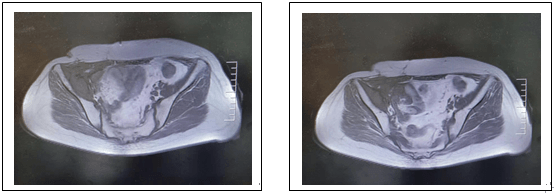

下圖為放療前病變及放療靶區(qū)